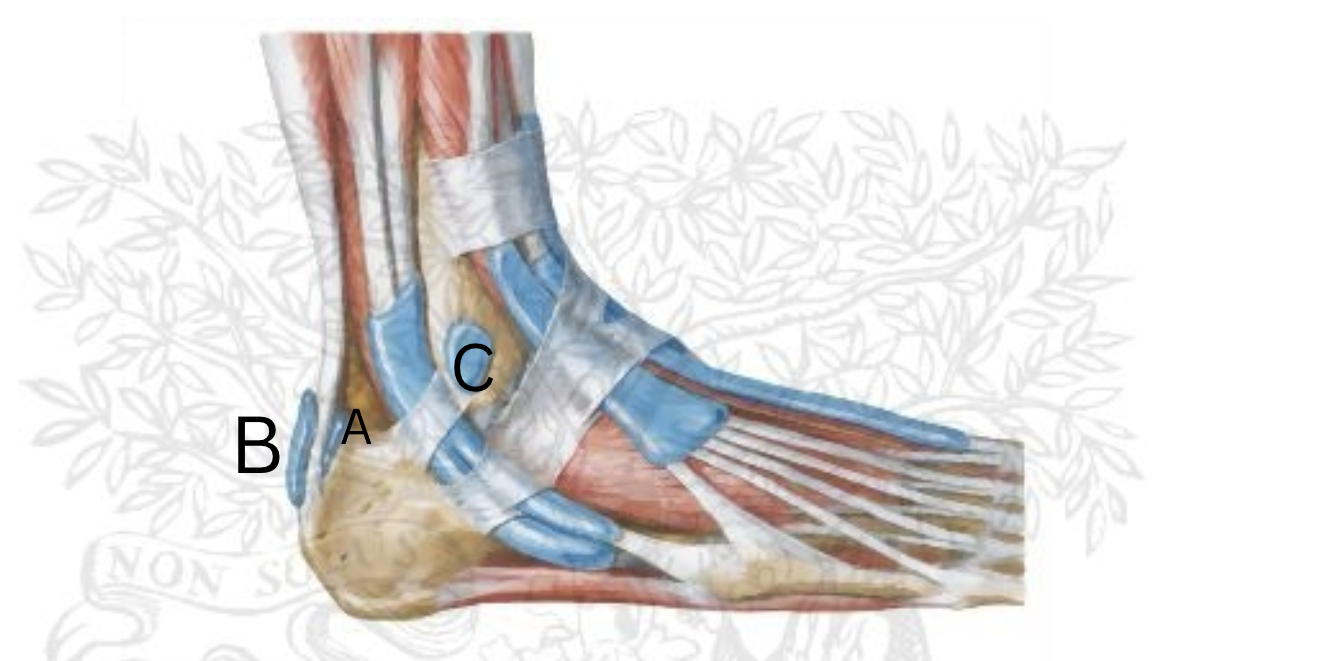

Label each ligament from A-D

A. Plantar Calcaneonavicular (Spring) Ligament (makes up arch)

B.Tibiocalcaneal Ligament

C. Posterior Tibiotalar Ligament

D. Anterior Tibiotalar Ligament

E. Tibionavicular Ligament